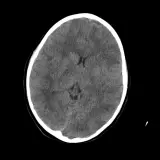

Over 2,100 interactive radiology cases, curated by radiologists for your level of training. Scroll, window, and view cases full screen — just like on PACS. Click linked findings in each writeup to jump straight to them on the image. Cases include sample reports, a focused discussion section, original illustrations, and videos.

PACSで期待されるツールを完備した完全インタラクティブな症例 — スクロール、ウィンドウ調整、ズーム、パン、計測、ROI、フルスクリーンモード。

重要な所見を症例画像上に直接ハイライトする豊富なアノテーション。症例解説内のリンクされた所見をクリックすると、スキャン上の正確な位置へジャンプできます。